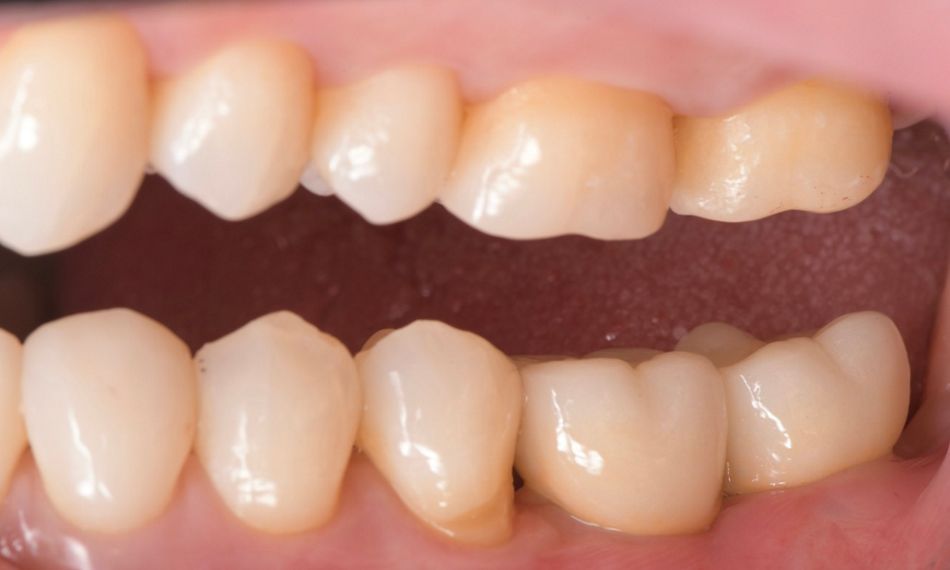

The gingiva was evaluated before the placement of the final prosthetics (Fig. 19). A fully polished zirconia prosthetic was then carefully fabricated and inserted, and torqued to 35 Ncm (Figs. 20,21) and the subsequent x-ray revealed satisfactory results (Fig. 22).

Fig. 19

Fig. 21

Fig. 20

Fig. 22

At the follow-up recall in 2021, the clinical evaluation indicated that the peri-implant soft tissues were in good health, with no signs of inflammation. Additionally, the marginal levels were appropriately maintained (Fig. 23).

Fig. 23